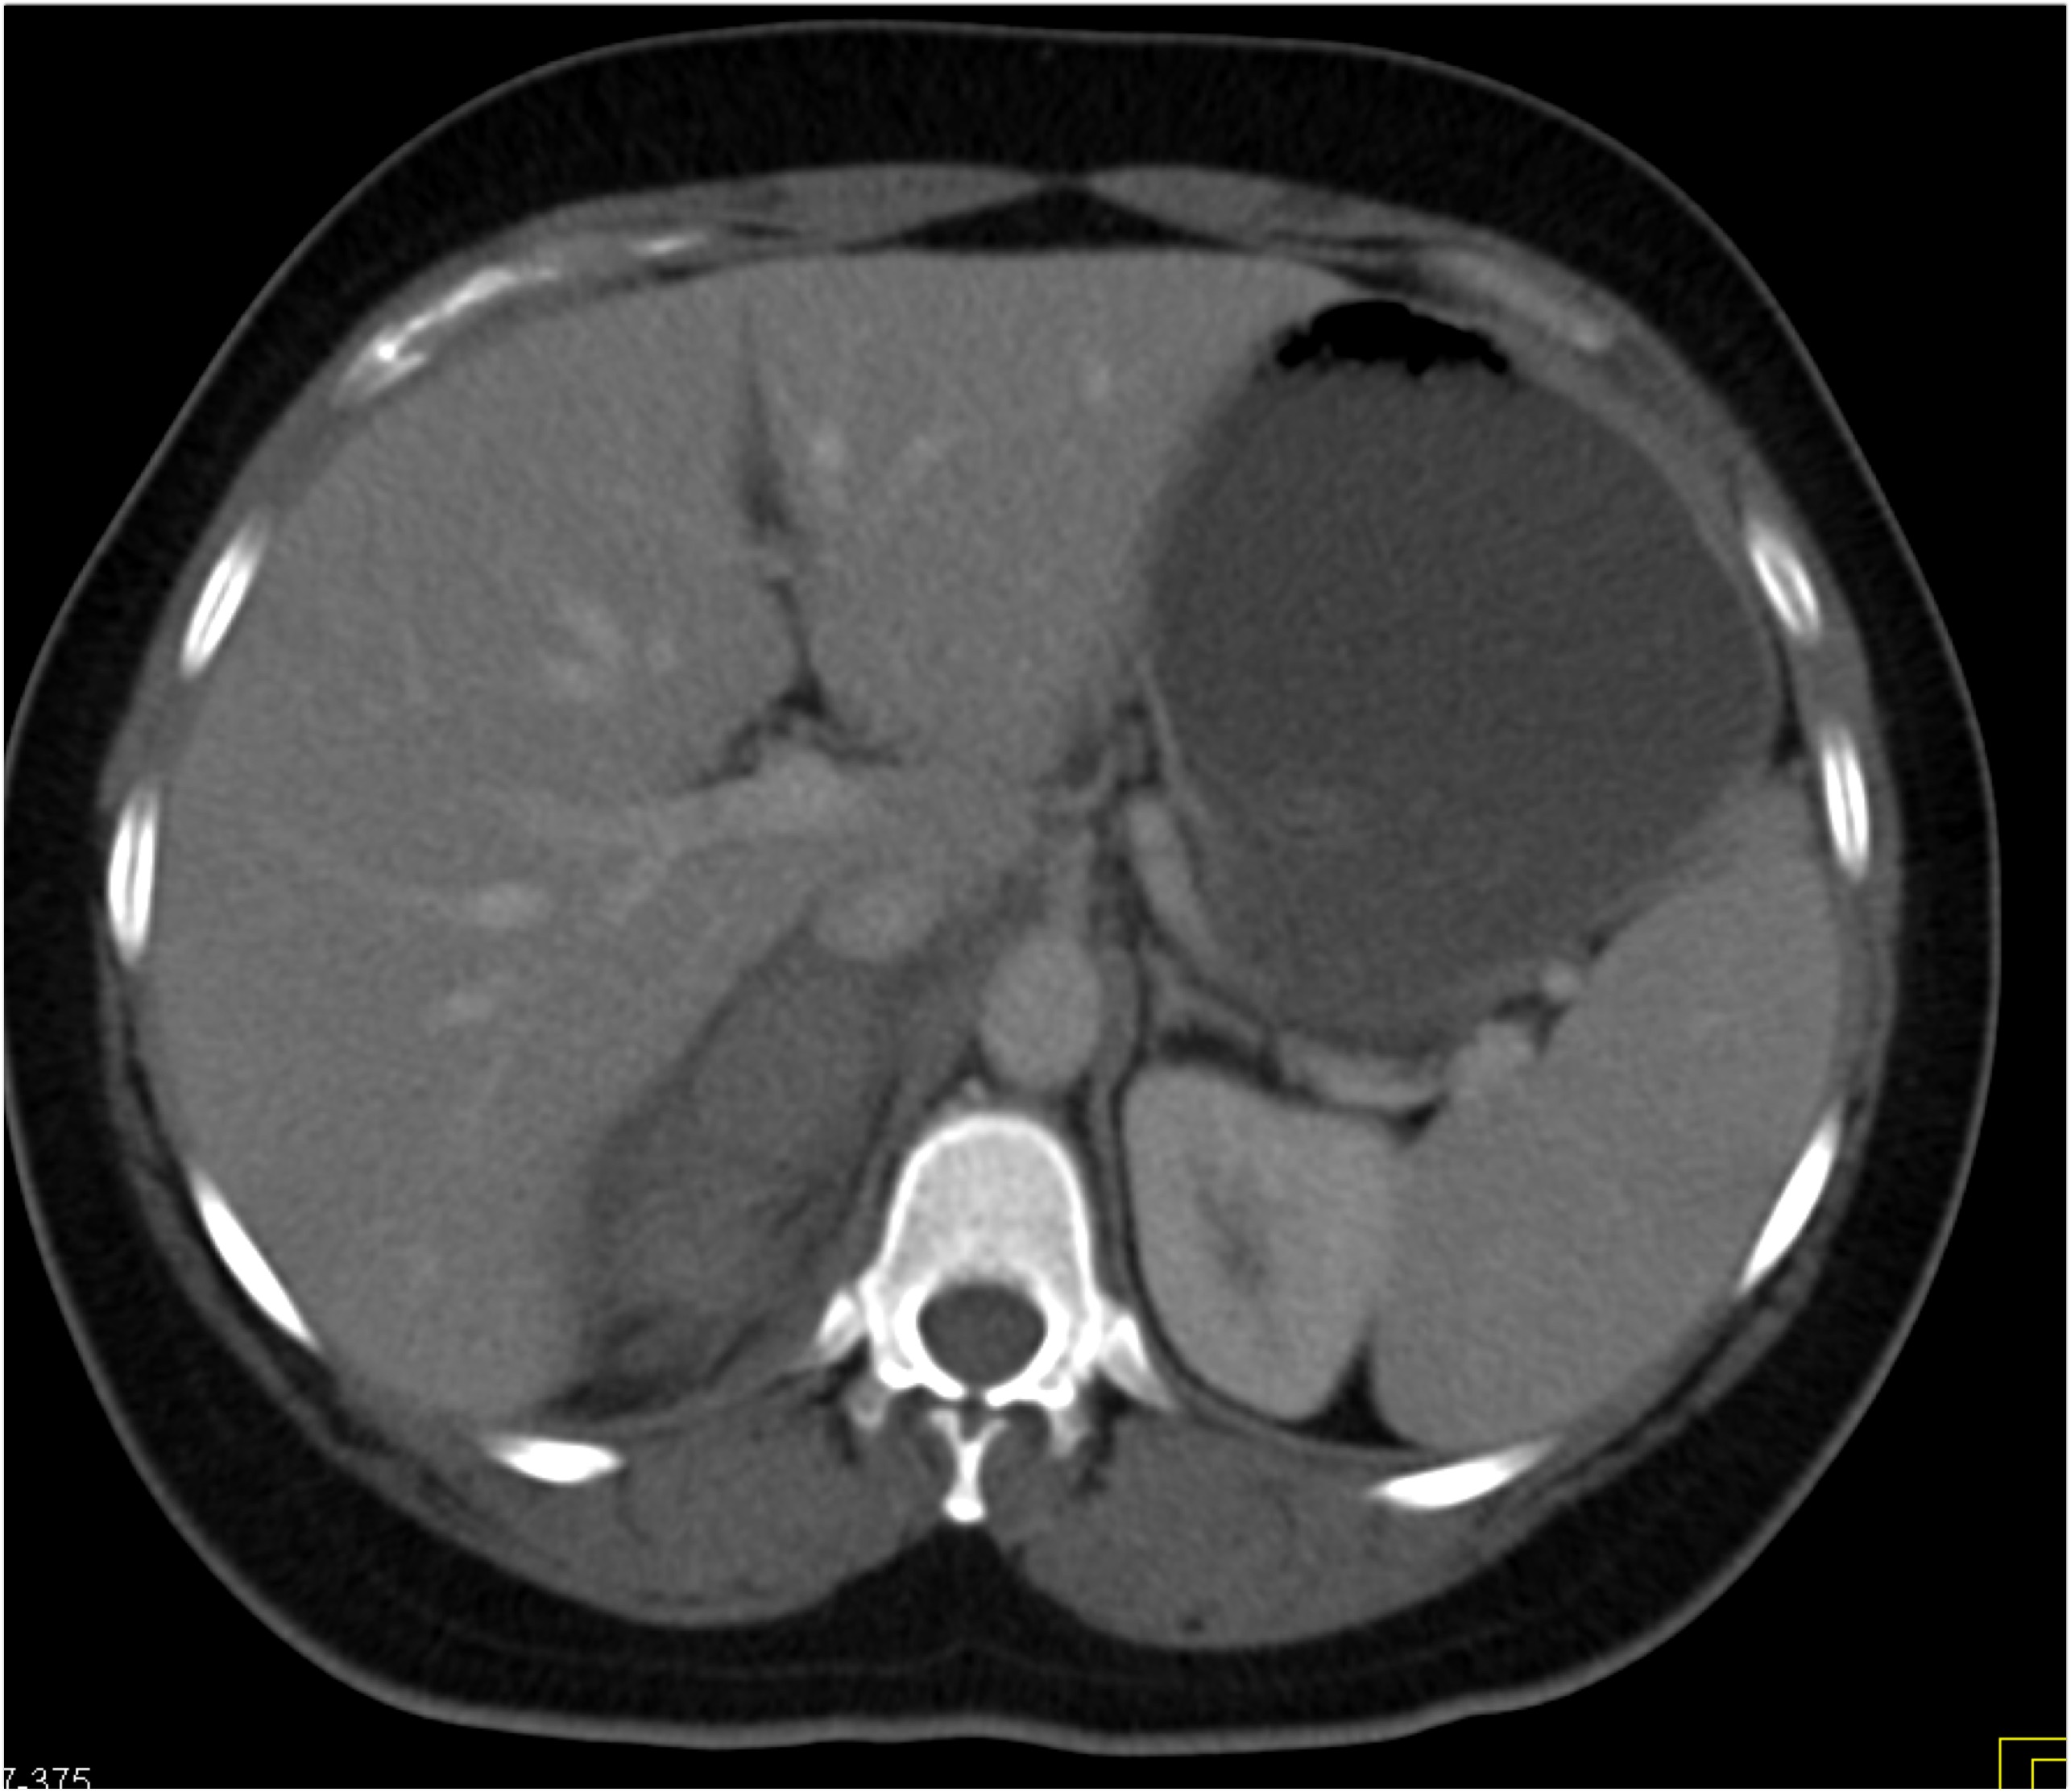

6) The most likely diagnosis in this case is?

lymphoma

acute pyelonephritis

XGP (xanthogranulomatous pyelonephritis)

TB